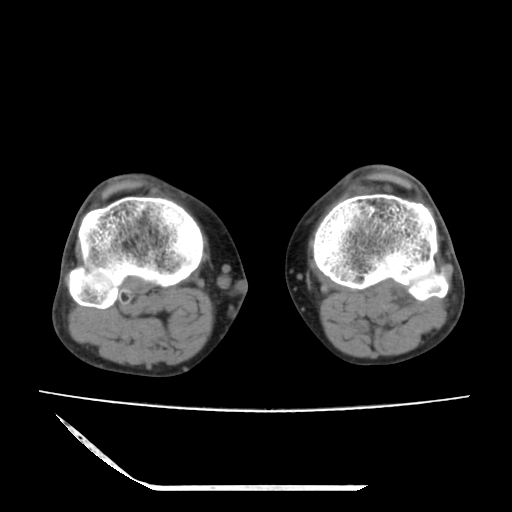

标题: CT13225:老年男性,左膝关节疼痛数月;请各位老师讨论。 [打印本页]

标题: CT13225:老年男性,左膝关节疼痛数月;请各位老师讨论。

骨质增生,骨性关节面硬化,关节积液,考虑退行性骨关节病

关节腔内少量积液,关节面退变。

双膝退变

骨质增生,骨性关节面硬化,关节间隙失常,关节积液,考虑退行性骨关节病.

这是由于两侧的肌肉不对称所致,加上扫描的平面也有些差异。请看示意图:

这个病例诊断:退行性骨关节炎